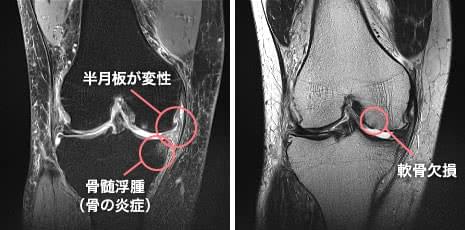

骨の形以外にも有益な情報がわかります

骨の変形がわかるレントゲンは変形性ひざ関節症と診断する上で一般的な検査ですが、ひざ関節の組織の状態が症状の程度に関係していることが多々あります。また、再生医療で改善は見込めるか、本当に適した治療は何なのかなどを検討する場合には、詳細情報が必要です。

MRIの高解像度の画像は、骨の内部や軟骨、半月板、靭帯の問題を可視化。また出血や炎症、腫瘍や水腫の有無も確認できます。磁気を利用しているので、他の画像検査のように放射線被爆がない点も特徴のひとつです。

実際の症例1

- 年齢・性別

- 58歳・男性

- お悩み

- 年齢的にヒアルロン酸とリハビリしかないと言われたが、強くなる痛みをどうにかしたい。

- 画像所見

- 半月板の一部が関節外に飛び出している。軟骨の一部欠損や骨のダメージもあり。

- 診断

- グレード3で変形し始めており、再生医療の適応と判断。ご本人も方法あるなら試したいと選択。